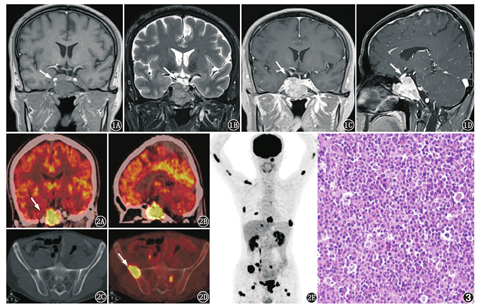

患者男,50岁,右眼外展受限8个月,视物模糊、重影10余天,加重伴头痛3 d入院。头颅MRI示斜坡、蝶窦及鞍内团块状稍长T1WI、等或稍短T2WI信号,增强扫描呈不均匀强化,垂体柄左偏,结论为"枕骨斜坡突向蝶窦及鞍内占位性病变,不除外脊索瘤"(图1)。患者2014年2月就诊时血钙、血肌酐均正常,RBC稍降低,为4.14[正常参考值(下同)4.30~5.80]×1012/L,血尿素为9.14(3.2~7.0) mmol/L。为进一步明确诊断,行18F-FDG PET/CT检查,结果(图2)显示:鞍区、斜坡区见放射性摄取增高肿块,大小约为3.4 cm×2.8 cm,SUVmax 28.9,该灶相邻骨质见破坏;除斜坡区骨质破坏伴局部软组织肿块外,头及躯干部另见24处放射性摄取增高灶,病变位于双侧肱骨及双侧股骨髓腔(9处)、骨盆骨(6处)、脊柱椎体及附件(4处)、双侧肋骨(3处)、颅底骨(1处)、右侧锁骨(1处),SUVmax 6.4~21.2,CT示其中10处病灶(左侧肋骨、脊柱及骨盆骨)见骨质破坏,余14处未见明显骨质破坏。PET/CT诊断:考虑MM或蝶窦恶性肿瘤伴骨转移癌均有可能。随后该患进行2次鼻咽镜活组织检查,病理(蝶窦和鼻咽)显示肿瘤细胞弥漫片状分布(图3),免疫组织化学染色结果:白细胞共同抗原(leukocyte common antigen, LCA) (+)、上皮膜抗原(epithelial membrane antigen,EMA)(局灶弱+)、CD20(-)、CD38(+)、CD138(部分+)、CD79a(+)、CD3(-)、MM基因1(+)、CD10(+)、细胞增殖核抗原Ki-67(80%~90%,+)。病理诊断为淋巴造血系统恶性肿瘤,考虑为间变型浆细胞瘤。明确诊断后给予患者局部放疗,同时进行了7疗程化疗。确诊4个月后复查血液及生化指标,结果显示患者出现中度贫血,PLT 55.0(100~300)×109/L、血钙1.94(2.25~2.75) mmol/L、血尿素12.31(2.9~7.1) mmol/L、肌酐543.0(44~133) μmol/L)、β2-微球蛋白1.61(2.14~4.06) mg/L,免疫球蛋白(IgG、IgA、IgM)和血(λ、κ)轻链均未见异常。患者后出现急性肾功能衰竭和电解质紊乱,于诊断8个月后死亡。

MM侵犯颅骨常见,但伴鞍区软组织肿块形成较少见。MM侵犯鞍区主要起源于周围的骨质或者是颞骨岩部、蝶骨的黏膜[3],临床表现与鞍区原发疾病相近。Khan等[4]的研究显示,至2012年MM侵犯鞍区的报道仅26例,临床表现为头痛、复视、视力缺损、上睑下垂和面部疼痛。由于临床表现和影像学缺乏特征性,易误诊。本例患者初始症状为头痛逐渐加重,伴有视力下降及复视,与垂体腺瘤表现很相似,MRI诊断考虑脊索瘤,PET/CT检查示除斜坡、鞍区高代谢肿块外,其余高代谢灶均位于骨骼,部分骨骼可见穿凿样骨质破坏,同时鞍区病灶相邻骨质有明显破坏,故首先考虑MM伴鞍区侵犯可能。但该患者影像学表现并非典型的MM表现,骨质疏松不明显,仅表现为散在的骨质破坏,FDG摄取程度很高,非常容易误诊为蝶窦原发恶性肿瘤伴多发骨转移或淋巴瘤。

近年来,18F-FDG PET/CT广泛应用于MM的全身评价,还可用于预后评估。MM因其细胞分化程度不同而FDG摄取程度不同,李现军等[5]总结的26例MM SUVmax为3.81±2.17,低于骨转移灶的代谢程度。本例为间变型浆细胞瘤患者,就诊初期肾功能损伤不明显,确诊4个月内贫血及肾功能损失明显加重,明确诊断8个月后死亡,说明该类型骨髓瘤恶性度较高,进展快,SUVmax可达28.9,也表明通过FDG摄取程度高低可以预测患者预后。PET/CT在本例中还发挥了全身显像和分子水平诊断的优势,发现了14处无骨质破坏的MM侵犯灶,有助于提供更加准确的临床分期。